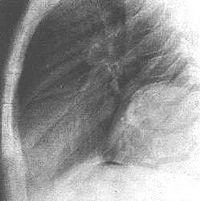

畸胎瘤大多数为外生性或有明显肿块可扪及,根据临床表现常能早期诊断。仔细的腹部体检和

肺部畸胎瘤造影

直肠指检,对腹部、盆腔、隐型骶尾部畸胎瘤的检查非常必要;肿瘤部位的X线平片可发现肿瘤内有骨、牙齿等异常钙化影而明确畸胎瘤,并多为成熟型畸胎瘤;胃肠道钡餐、钡剂灌肠静脉肾盂造影可了解相应部位的胃肠道或肾脏输尿管膀胱等脏器的受压推移情况。对生长迅速、浸润范围较广的畸胎瘤病例应进行CT核磁共振检查,以明确肿瘤浸润范围及与重要血管脊髓神经的相邻关系。